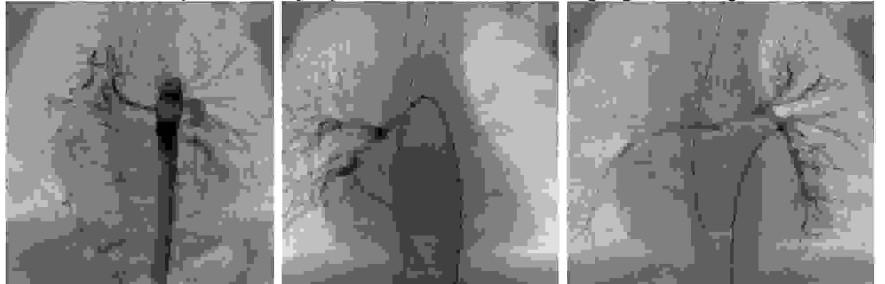

Pytanie 98

Wskaż prawidłowy opis obrazu badania angiograficznego: